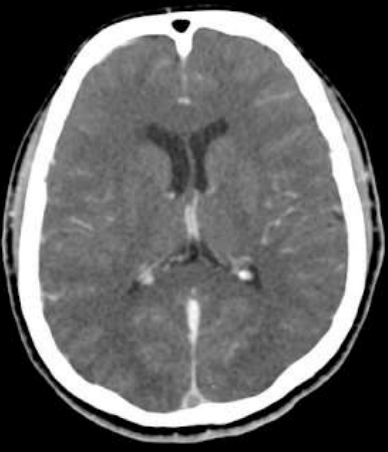

Paciente de 25 anos, sexo feminino, previamente hígida, fazendo uso apenas de anticoncepcional oral, é internada em uma unidade de urgência com cefaleia de forte intensidade, refratária ao tratamento medicamentoso. Realizou exame de imagem (Tomografia computadorizada de crânio com contraste) que demonstrou o seguinte achado:

Assinale a alternativa que apresenta o diagnóstico mais provável baseado na história clínica e achado de imagem.